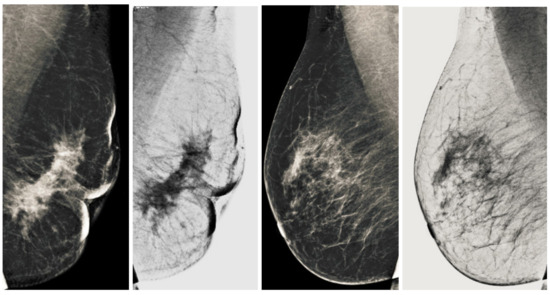

We also measured the PSNR, the image contrast, and the EME of each category of databases, as we analyzed the image in terms of visual observation. The Table 3 shows the performance of our proposed image enhancement method. It can be seen from the Table 3 that our proposed method improved PSNR, contrast, and EME, and this also shows that our method can work on every category of BI-RADS. Because many techniques do not work on higher grade BI-RADS due to the complexity and the images are not of good quality. We obtained an average improvement in PSNR, contrast, and EME in the Table 4. For more observations, we analyzed the visual image of each category and we analyzed the CC and MLO of each category as shown in the Figure 7, Figure 8, Figure 9, Figure 10, Figure 11, Figure 12, Figure 13, Figure 14, Figure 15 and Figure 16. From the figures, every detail of image of every category can be observed, leading to better segmentation of the abnormal region. This image enhancement technique can be used as preprocessing steps for the detection of breast cancer. It is a very fast processing algorithm and it takes on 21.13 s. It gives opportunity to medical experts to analyze the mammogram images very quickly to propose the timely treatment.

Figure 11.

Analysis of CC view of BI-RADS-3 mammogram images.

Figure 12.

Analysis of MLO view of BI-RADS-3 mammogram images.

Figure 13.

Analysis of CC view of BI-RADS-4 mammogram images.

Figure 14.

Analysis of MLO view of BI-RADS-4 mammogram images.